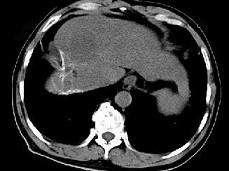

问题 女性,56岁,腹胀、双下肢浮肿、乏力、食欲不振,影像所见如下图,最佳的诊断是()

选项 A.酒精性肝硬化并肝血管瘤 B.血吸虫肝硬化并肝癌 C.肝炎后肝硬化并肝癌 D.局限性脂肪肝 E.原发性肝癌

答案 B